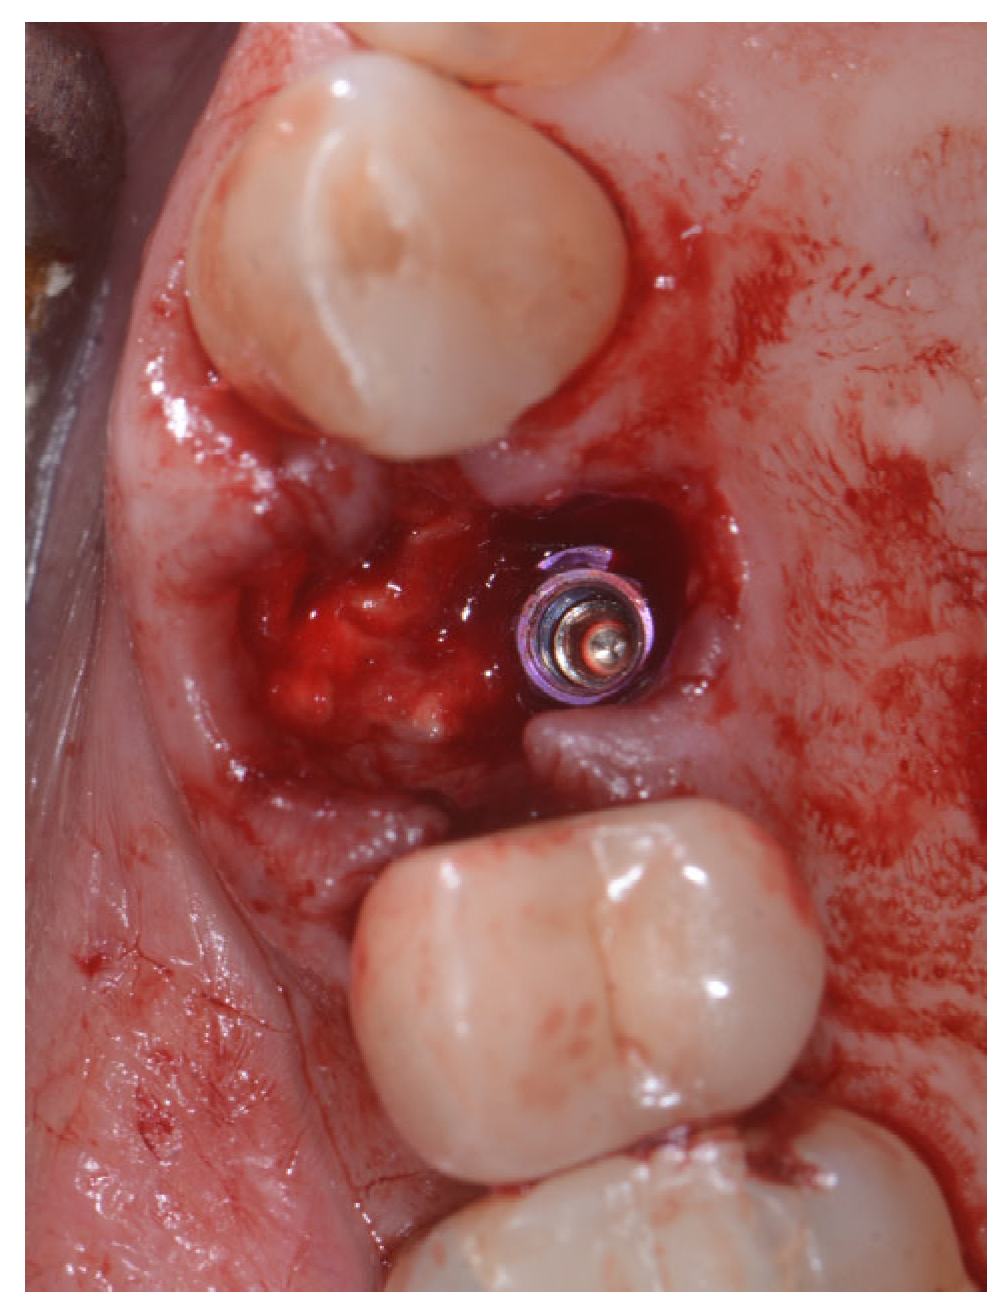

2.2. Surgical Technique

2.3. Indications

- Sockets that allow simultaneous implant placement;

- Sockets with intact buccal bone;

- Sockets with buccal fenestration.